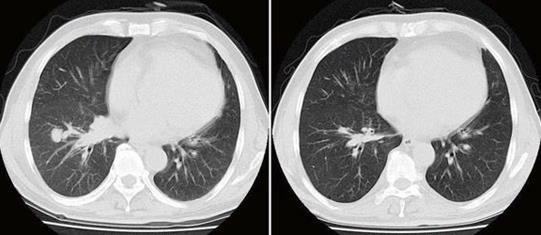

小细胞肺癌化疗后病灶消失

对于小细胞肺癌的患者来说,由于小细胞肺癌具有易转移、对化疗的短期有效率较好的特点,所以不论病情是早期还是晚期,化疗均是其主要的治疗方法。